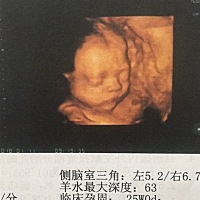

大家帮忙看看,这是男宝还是女宝宝